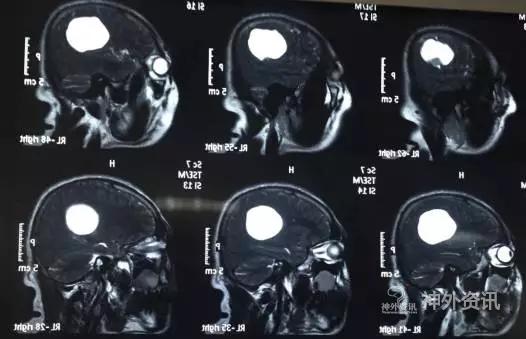

头颅MR示:右颞顶囊性占位伴结节,考虑胶质瘤可能。MRI T1为等信号(图1);T2囊液为高信号(图2);结节为均匀增强(图3);弥散相显示弥散受限(图4)。

图3. 结节为均匀增强。